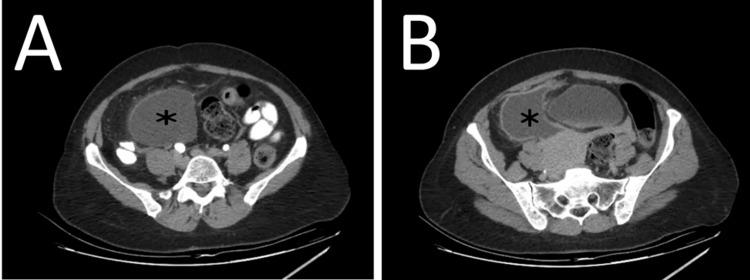

Hydatid cyst is a parasitic zoonosis caused by echinococcosis. Liver and lung are the two primarily affected organs. Primary mesenteric hydatid cyst is a rare event, and few cases have been reported globally. In this case report, we present the first documented case, to our knowledge, in Lebanon. The patient was a 49-year-old female who presented for acute worsening of a long-standing abdominal pain. The primary differential diagnosis was an ovarian cyst, for which urgent surgical excision was performed. Histopathological analysis showed a primary mesenteric hydatid cyst, thus providing the final diagnosis. This case highlights the diagnostic challenges that rare and atypical localizations of hydatid cysts present, and the importance of including echinococcosis in the differential diagnosis of abdominal cystic masses.

摘要

包虫囊肿是由棘球蚴病引起的一种寄生虫人畜共患病。肝脏和肺是两个主要受累器官。原发性肠系膜包虫囊肿是一种罕见的情况,全球报道的病例很少。在本病例报告中,据我们所知,我们呈现了黎巴嫩的首例有记录的病例。患者为一名49岁女性,因长期腹痛急性加重前来就诊。主要鉴别诊断为卵巢囊肿,为此进行了紧急手术切除。组织病理学分析显示为原发性肠系膜包虫囊肿,从而得出最终诊断。该病例突出了包虫囊肿罕见和非典型定位所带来的诊断挑战,以及在腹部囊性肿块的鉴别诊断中纳入棘球蚴病的重要性。